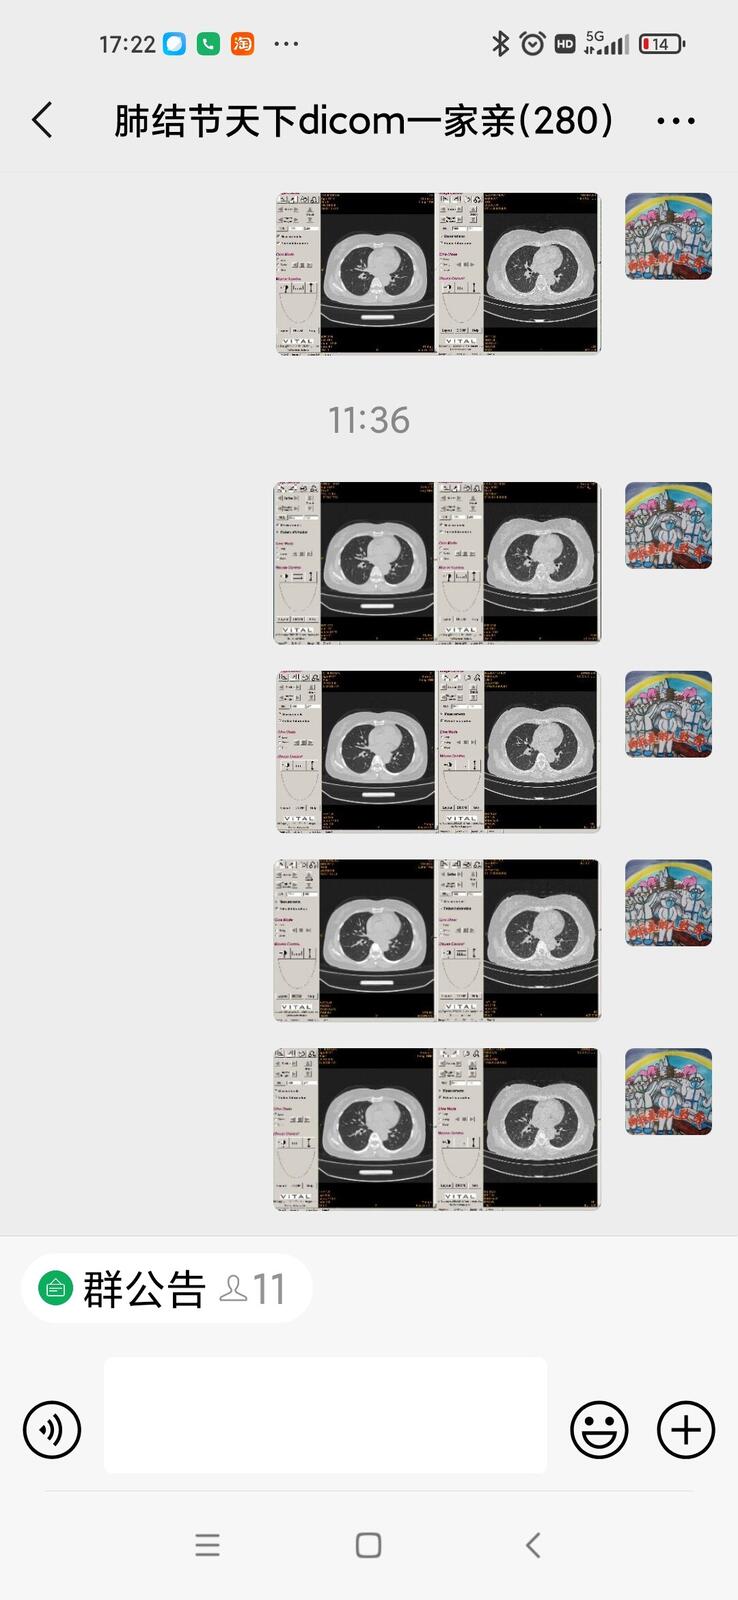

只言片语 之 (7)